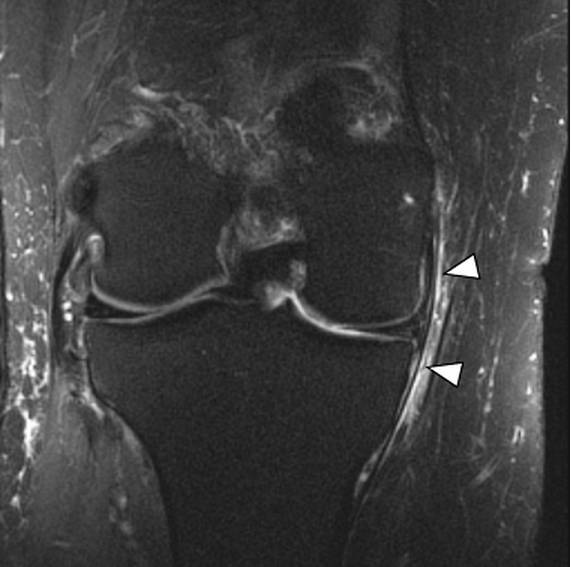

内侧副韧带损伤时MRI的典型表现包括韧带深浅两层间的滑膜囊肿胀、皮下软组织肿胀、内侧副韧带撕裂与周围血肿。韧带纤维的损伤可从单纯的排列紊乱到完全撕裂(图5~图8)。其他MRI表现有关节腔积血、股骨外侧髁或胫骨平台挫伤、半月板损伤、其他韧带损伤、以及股骨内侧髁的部分撕脱骨折(极为少见)。MRI的冠状位图像可很好地观察内侧副韧带及后内侧角。

图7,内侧副韧带II级损伤。韧带部分撕裂,内侧副韧带深层浅层纤维均可见高信号水肿影(箭头所示)。

图8,内侧副韧带III级损伤。内侧副韧带完全横行撕裂,箭头所示位置为正常黑色韧带纤维局部断裂区域,此区域血肿水肿包绕内侧副韧带。韧带纤维撕裂部位不平整。需注意区分高等级的II级撕裂与III级撕裂。